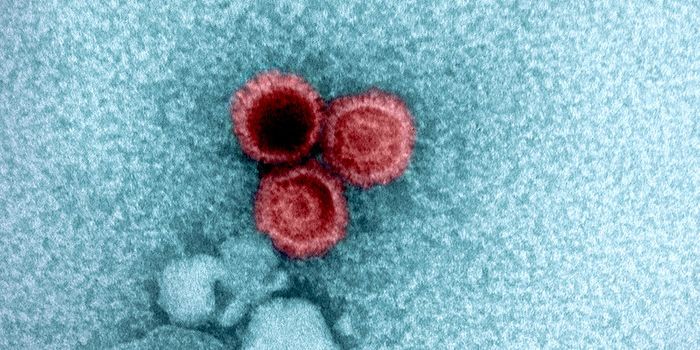

SEP 08, 2024MicrobiologySARS-CoV-2, the pandemic virus that causes COVID-19, has mutated endlessly since it burst on the scene in late 2019. An ...

AUG 27, 2024MicrobiologySince the start of the COVID-19 pandemic, the virus that causes the illness - SARS-CoV-2 - has had a practically infinit ...